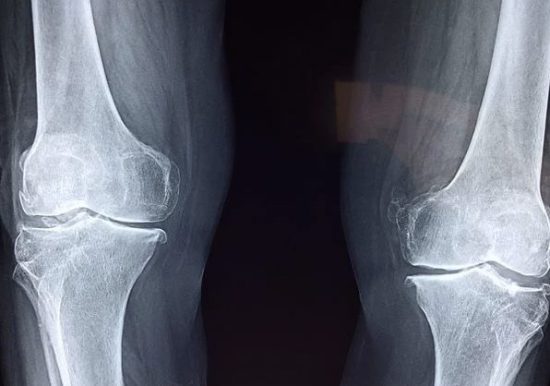

De la combinación de ambos materiales se obtiene una estructura cristalina extremadamente dura: alúmina porosa. Con este material, podrían elaborarse implantes permanentes que faciliten la formación de nuevo tejido óseo. De esta forma, se presenta como un tratamiento alternativo de roturas y fisuras de huesos.

La alúmina es un material muy resistente y capaz de estimular la generación del nuevo tejido y establecer enlaces químicos con él. Por este motivo, se emplea habitualmente para desarrollar prótesis para las articulaciones e implantes dentales, entre otros usos.

Sin embargo, tal y como se indica en nota de prensa Fundación Descubre, esta estructura cerámica cada vez se utiliza menos con finalidad clínica debido al surgimiento de otros materiales comerciales muy duraderos y con alta resistencia a los procesos químicos y al óxido como el titanio macizo, que sirve para elaborar válvulas cardíacas o prótesis de rodilla; así como el acero inoxidable, que se emplea en prótesis temporales. No obstante, estos sustitutos poseen una superficie menos porosa y difícil de penetrar. Por este motivo, en ocasiones presentan problemas para que el organismo los acepte y se producen cicatrices en la masa ósea o el rechazo al material.

Los expertos explican que enfocaron la elaboración de la alúmina al tratamiento de fisuras en el hueso cortical, es decir, la parte más dura y externa del mismo, como el área inferior del fémur.